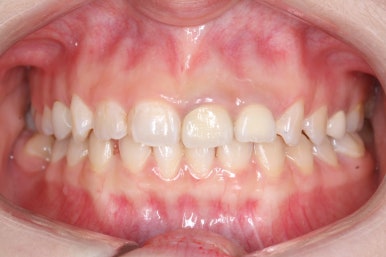

초진 때의 입안 모습입니다.

앞니는 고른 편이였으나 군데군데 틈새가 있었습니다. 약간 삐뚠 모습도 보이지만 환자분께서 개선을 하고자 했던 부분은 아래쪽 어금니 1개가 없는 자리였습니다.